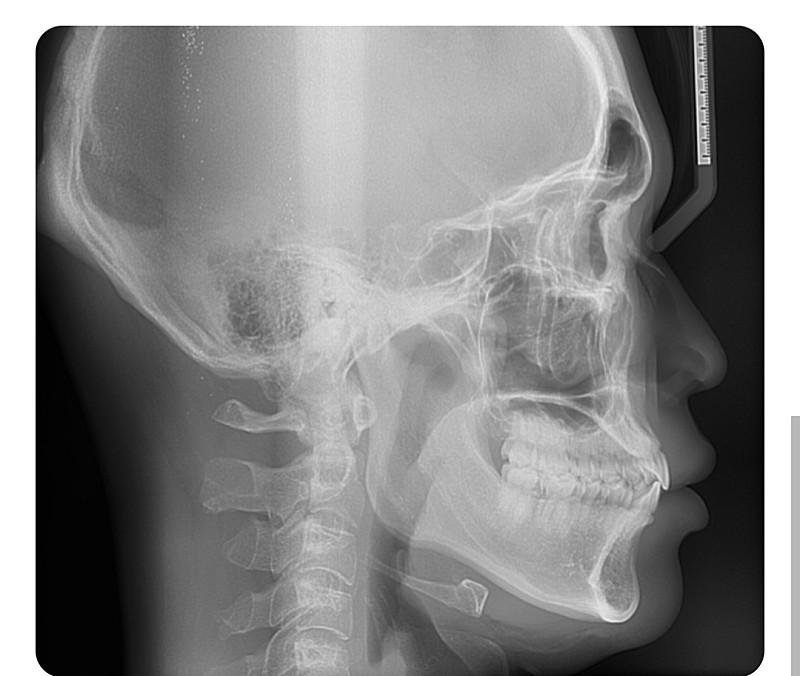

골격과 치아 문제는 아닌 것으로 보입니다. 또한 어느 누구도 입을 다물면 아래턱에 힘이 들어가는 것은 당연합니다. 이는 폐구근에 의해 나타나는 정상적인 생리 반응입니다. 다만 본인이 느끼기에 너무 불편하다고 판단이 된다면 대학병원 방문 후 구강내과를 한 번 방문해보시길 바랍니다.